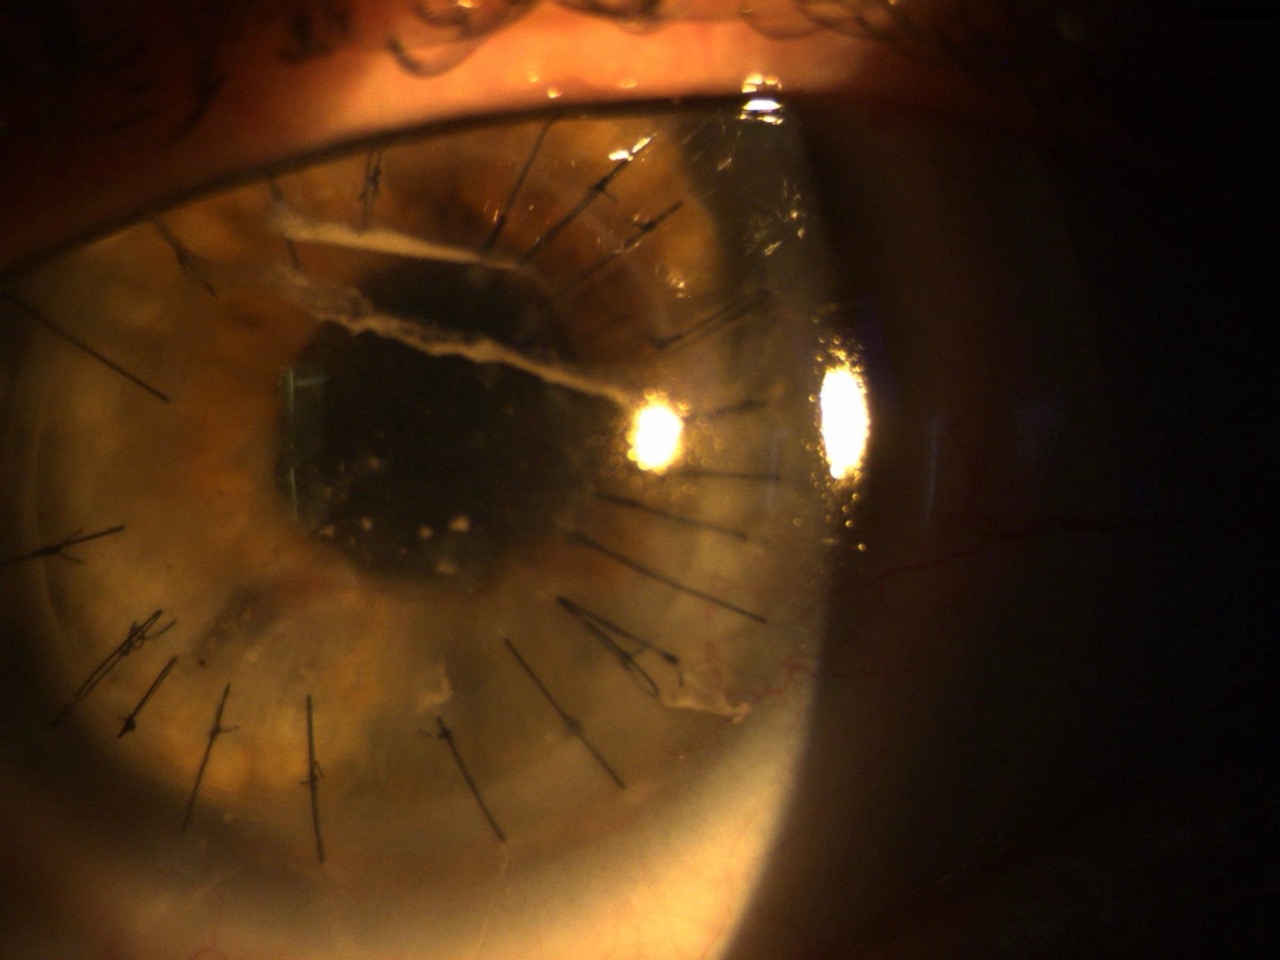

Condition after perforating keratoplasty (PKP)

After corneal transplants, it is not uncommon for severe astigmatism or topographical irregularities to occur. Suture tension, graft size, and postoperative remodeling often lead to a complex height profile. Often, the preoperative prolonged cornea becomes an oblong cornea after surgery, which means it has flatter central radii and steeper peripheral radii. While RGP corneal lenses can be perfectly functional for PKP patients, practitioners often face challenges such as pressure near the transplant, microerosions, or contact lens decentration. Scleral lenses can be used to bridge the irregular cornea (vault) and achieve a uniform vault structure over the transplant. This not only reduces mechanical stress to a minimum, but also creates an optically customizable zone.

Corneal lenses ideally position themselves on the tear film in front of the cornea with sufficient pupil coverage. The fit is assessed in terms of surface fit by observing the tear film stained with a sodium fluorescein solution. The main variable here is the tear film thickness, which can fluctuate with increased tear secretion after insertion of the corneal lens. In cases of regular or only slightly irregular corneas, varying tear thicknesses under the contact lens do not pose any biomechanical problems. However, in cases of severely irregular corneas, there are risks ranging from pressure points over cone tips and epithelial compression to corneal damage. If hard apical or paracentral contact points occur during corneal lens fitting in cases of irregular corneal conditions, the localized mechanical stress on the cornea can become so high that it results in stainable areas with spots or even deep corneal lesions.

When assessing the fit of scleral lenses, sodium fluorescein solution is used to estimate corneal bridging using a slit lamp. To do this, the narrow slit can be observed at a 45° angle and the thickness of the fluorescein layer can be compared to other known measurements, such as lens thickness.

Since scleral lenses rest exclusively on the bulbar conjunctiva in the scleral area, it is important to note when assessing fit that the estimated or measured corneal curvature is highest after initial insertion and decreases with prolonged wear due to compression of the bulbar conjunctiva. A good starting value for central corneal bridging is between 250 and 350 µm.